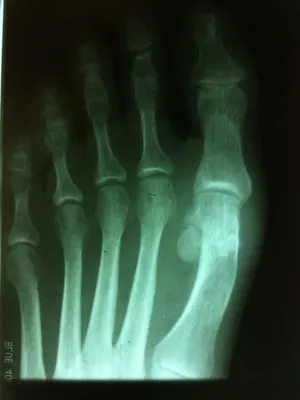

Avulsion Fracture of Lateral Collateral Ligament causing Hallux Varus, THe fractue can be seen to the right of the 1st metatarsal head.